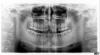

anvladd Опубликовано 23 апреля, 2013 Поделиться Опубликовано 23 апреля, 2013 (изменено) коллеги,как бы вы поступили? я планирую удалить 11 и 21,мост 13,12-21,22(мк или циркон 3shape) оптг позже,не грузится. Изменено 23 апреля, 2013 пользователем anvladd Ссылка на комментарий

anvladd Опубликовано 24 апреля, 2013 Автор Поделиться Опубликовано 24 апреля, 2013 ОПТГ Ссылка на комментарий

kriokov Опубликовано 24 апреля, 2013 Поделиться Опубликовано 24 апреля, 2013 (изменено) пациентка соматически здорова? Такое впечатление по орто , что кость генирализовано уходит, где больше, где меньше Изменено 24 апреля, 2013 пользователем kriokov Ссылка на комментарий

IvanK Опубликовано 25 апреля, 2013 Поделиться Опубликовано 25 апреля, 2013 На 16 и 15 зубной камень, сколько еще его можно найти не известно.. такие "треугольники" между зубами очень характерны для любителей зубочисток. ИМХО Ссылка на комментарий

Demerchyan26 Опубликовано 25 апреля, 2013 Поделиться Опубликовано 25 апреля, 2013 На 16 и 15 зубной камень, сколько еще его можно найти не известно.. такие "треугольники" между зубами очень характерны для любителей зубочисток. ИМХО Там еще стираемость зубов, для такого возраста зубки стерлись прилично. 1 Ссылка на комментарий

x4ex Опубликовано 25 апреля, 2013 Поделиться Опубликовано 25 апреля, 2013 не от того ли стираемость, что отсутствует резцовое и клыковое ведение?интересно, отчего уехали вперед центральные резцы... Ссылка на комментарий